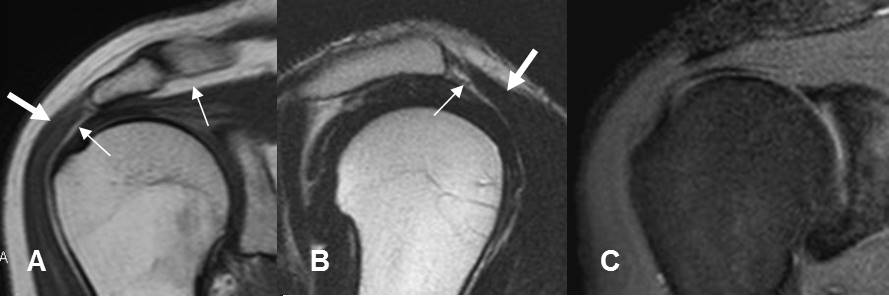

Fig 4. LCA normal.

A: RM sagital en T1, B: RM sagital en T2 y C: RM sagital en GE. Fibras hipointensas en todas las secuencias en un ligamento normal y rodeado por grasa.